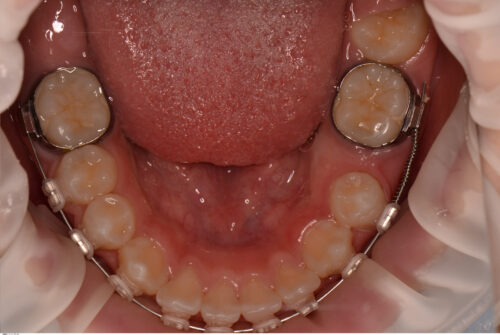

まずはオープンコイルで萌出するためのスペースを拡大していきます。

スペースができたら粘膜を切開して装置を接着しゴムで引っ張ります。